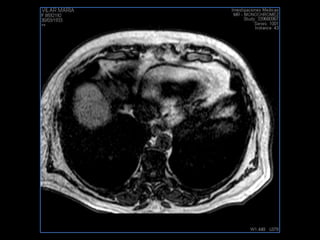

PROTOCOLO hígado graso AXIAL in phase y out phase AX T1 y AX fat sat +SAG T2  CON   GADOLINIO :  COR T1+AX T1(DIN) SAT: NO  FASE: RL THK: 4MM  COIL:  GAP: (FACTOR 1.4)  FOV: 40 CM NEX:2 SINCRONIZACION RESPIRATORIA EN 3 O 4 CICLOS ALE

PROTOCOLO hemocromatosis AXIAL supresión grasa /AX multieco en higado COR T2 AX T1 +SAG T2  CON   GADOLINIO :  COR T1+AX T1 SAT: NO  FASE: RL THK: 4MM  COIL:  GAP: (FACTOR 1.4) 1MM FOV: 40 CM NEX:2 SINCRONIZACION RESPIRATORIA EN 3 O 4 CICLOS ALE